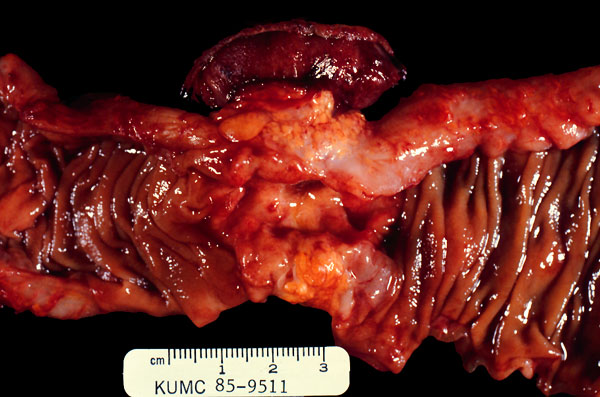

Carcinoma of the sigmoid colon

The tumor has a typical napkin ring appearance concentrically narrowing the lumen of the large intestine.